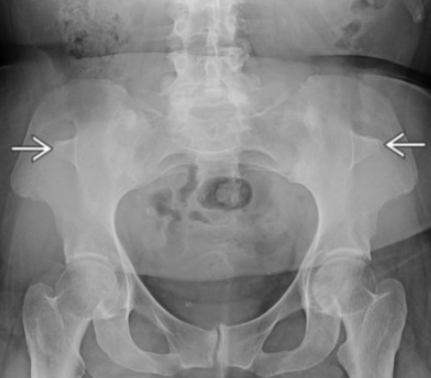

• Imaging Findings

• Bilateral posterior iliac horns (Fong prongs)

• Flared iliac crest with protuberant iliac spines

• Apparently if you are shown the iliac horns alone that is enough to diagnose, don’t need to see the patellas